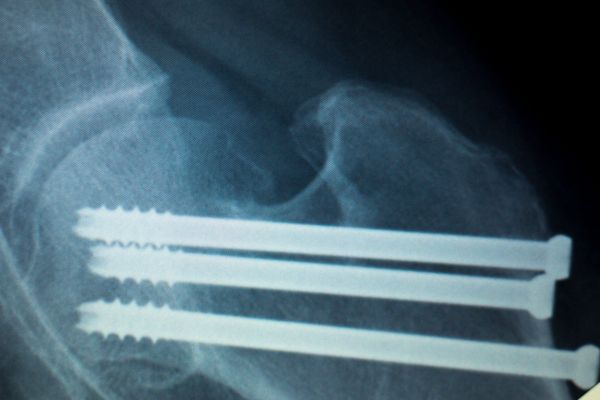

- Medical Devices: PLA’s biocompatibility and ability to degrade harmlessly make it suitable for certain medical applications, such as sutures and implants like rods and screws. Its use in medical devices aligns with the growing emphasis on sustainable practices in the healthcare industry.